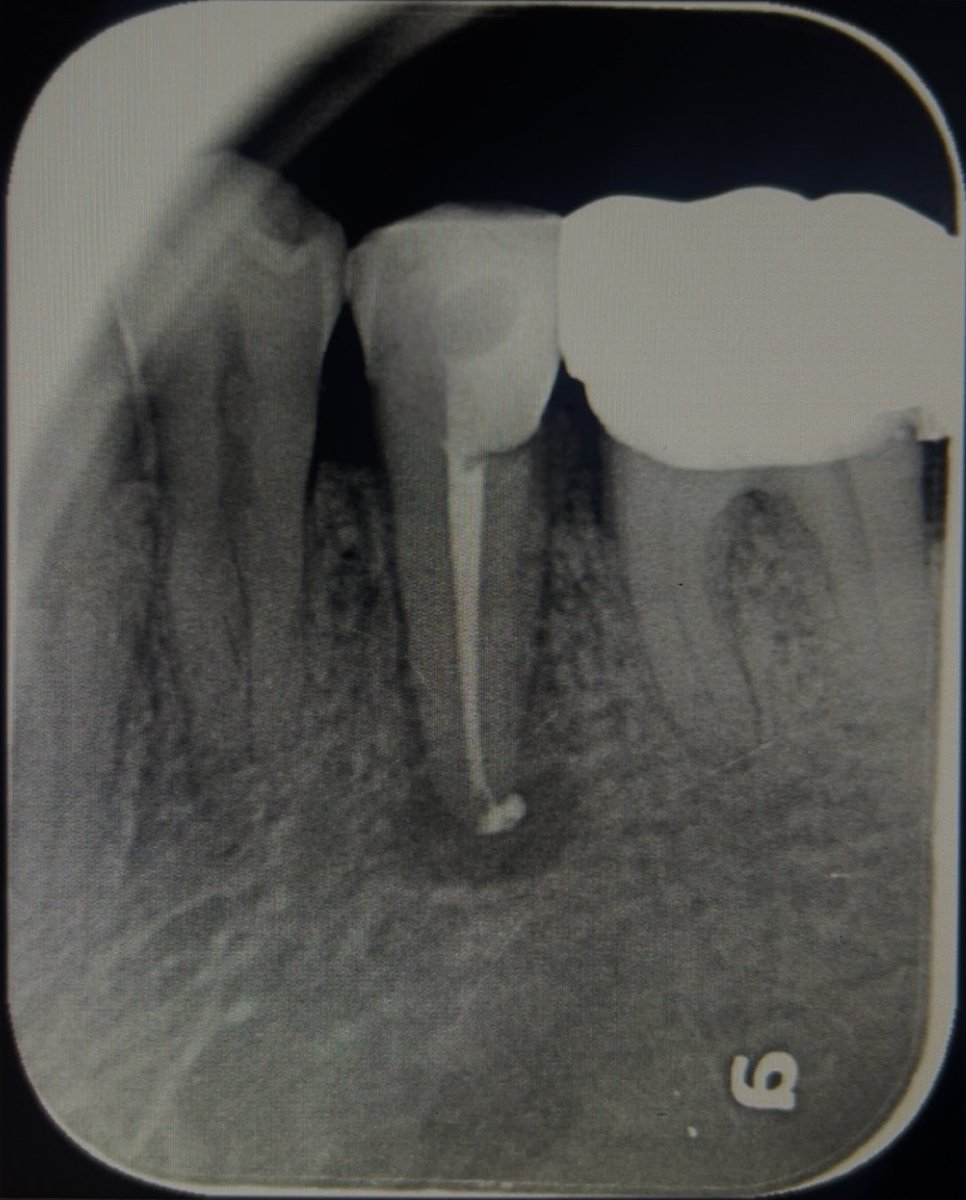

Today’s case:

Rct of #11 Dx : PI/AAA

• 1st visit: Open access, irrigation, abscess drainage, and dressing the canal with Ca(OH)₂.

• 2nd visit (after 30 days): Reopening the tooth, irrigation performed; the canal was completely dry and ready for obturation.

Patient is fine😁